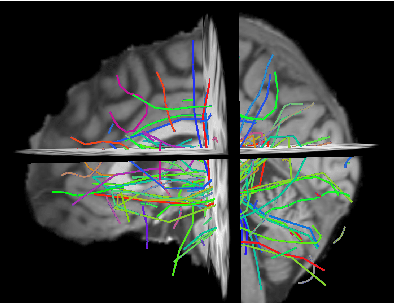

Abstract:Diffusion magnetic resonance imaging (dMRI) and tractography provide means to study the anatomical structures within the white matter of the brain. When studying tractography data across subjects, it is usually necessary to align, i.e. to register, tractographies together. This registration step is most often performed by applying the transformation resulting from the registration of other volumetric images (T1, FA). In contrast with registration methods that "transform" tractographies, in this work, we try to find which streamline in one tractography correspond to which streamline in the other tractography, without any transformation. In other words, we try to find a "mapping" between the tractographies. We propose a graph-based solution for the tractography mapping problem and we explain similarities and differences with the related well-known graph matching problem. Specifically, we define a loss function based on the pairwise streamline distance and reformulate the mapping problem as combinatorial optimization of that loss function. We show preliminary promising results where we compare the proposed method, implemented with simulated annealing, against a standard registration techniques in a task of segmentation of the corticospinal tract.

Abstract:Diffusion magnetic resonance imaging (dMRI) data allow to reconstruct the 3D pathways of axons within the white matter of the brain as a tractography. The analysis of tractographies has drawn attention from the machine learning and pattern recognition communities providing novel challenges such as finding an appropriate representation space for the data. Many of the current learning algorithms require the input to be from a vectorial space. This requirement contrasts with the intrinsic nature of the tractography because its basic elements, called streamlines or tracks, have different lengths and different number of points and for this reason they cannot be directly represented in a common vectorial space. In this work we propose the adoption of the dissimilarity representation which is an Euclidean embedding technique defined by selecting a set of streamlines called prototypes and then mapping any new streamline to the vector of distances from prototypes. We investigate the degree of approximation of this projection under different prototype selection policies and prototype set sizes in order to characterise its use on tractography data. Additionally we propose the use of a scalable approximation of the most effective prototype selection policy that provides fast and accurate dissimilarity approximations of complete tractographies.